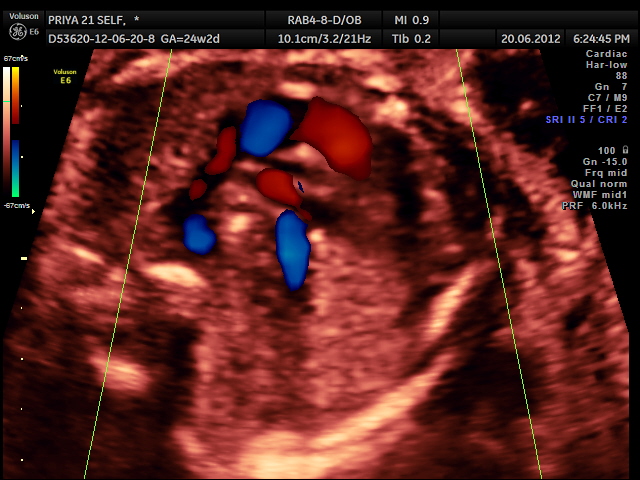

RV outflow tract with dilated Pulmonary trunk dividing into the Rt Pulm artery and the ductus seen. Aorta is not made out. ; SVC is seen